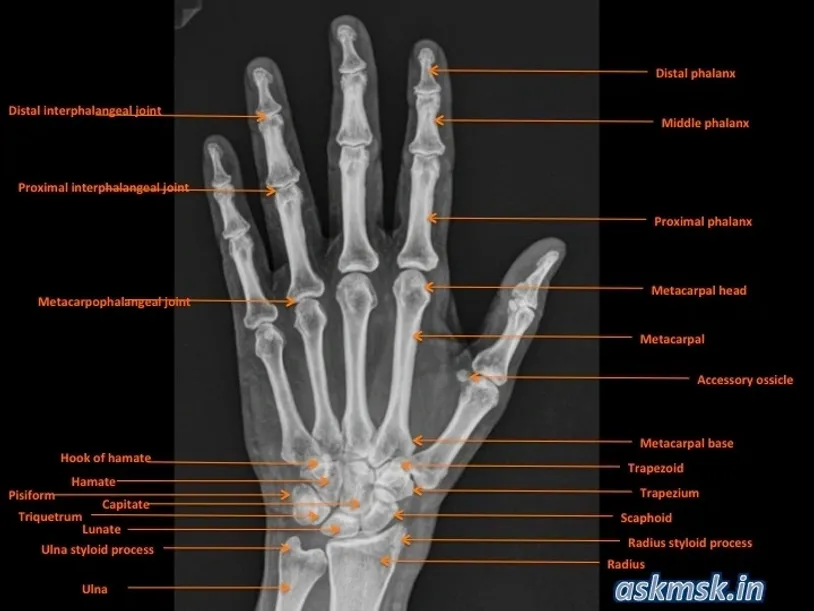

Anatomy Spotlight: What’s in the Frame?

The hand and wrist are complex yet elegant structures, comprising:

- Hand: 27 bones, including the phalanges (14), metacarpals (5), and associated joints.

- Wrist (carpus): 8 carpal bones arranged in two rows:

- Proximal row: Scaphoid, lunate, triquetrum, pisiform.

- Distal row: Trapezium, trapezoid, capitate, hamate.